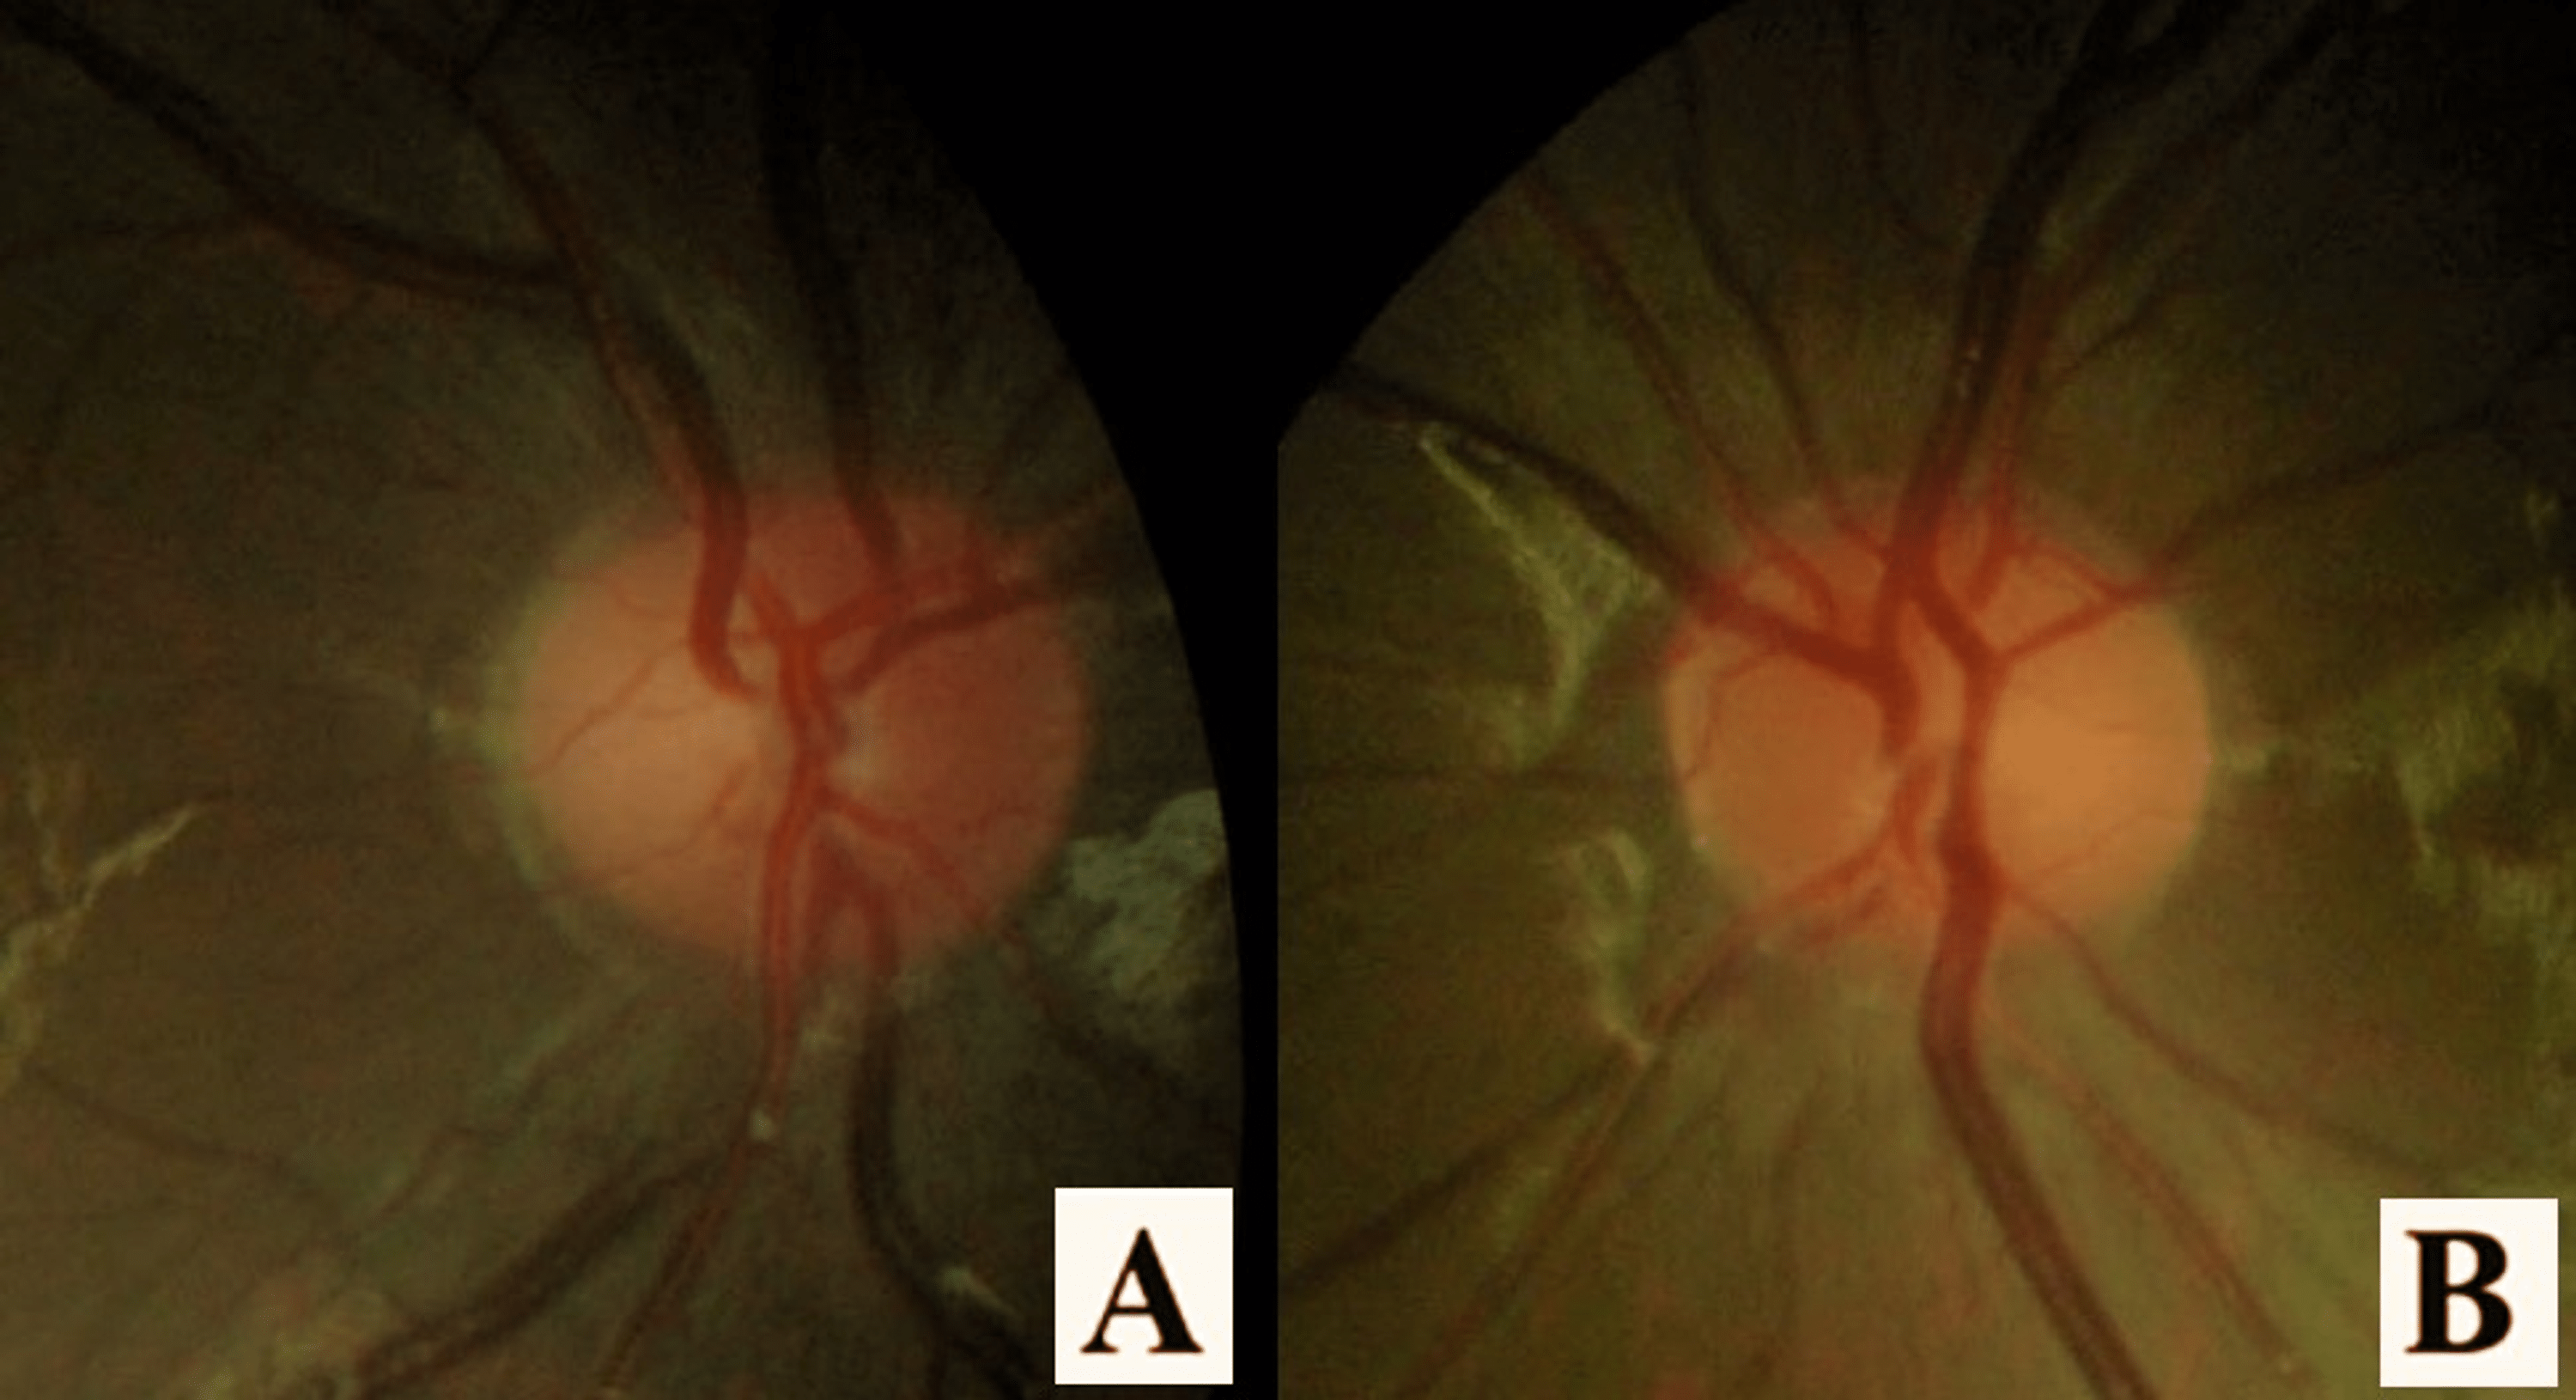

Binocular Optic Neuritis in an EightYearOld Boy Due to COVID19 Binocular Optic Neuritis The optic nerve carries light signals from the back of your eye to your brain so you can see. Optic neuritis (on) may involve the retrobulbar (retrobulbar neuritis) or the intrabulbar (papillitis). Experts go over the various causes of optic neuritis and the diagnostic. the clinical diagnosis of on consists of the classic triad of visual loss, periocular pain. Binocular Optic Neuritis.

(PDF) Binocular Optic Neuritis in an EightYearOld Boy Due to COVID19 Binocular Optic Neuritis Monocular, subacute loss of vision associated with orbital pain worsening on. The optic nerve carries light signals from the back of your eye to your brain so you can see. diagnosis and management of optic neuritis. diagnostic criteria for optic neuritis. Experts go over the various causes of optic neuritis and the diagnostic. the clinical diagnosis of. Binocular Optic Neuritis.